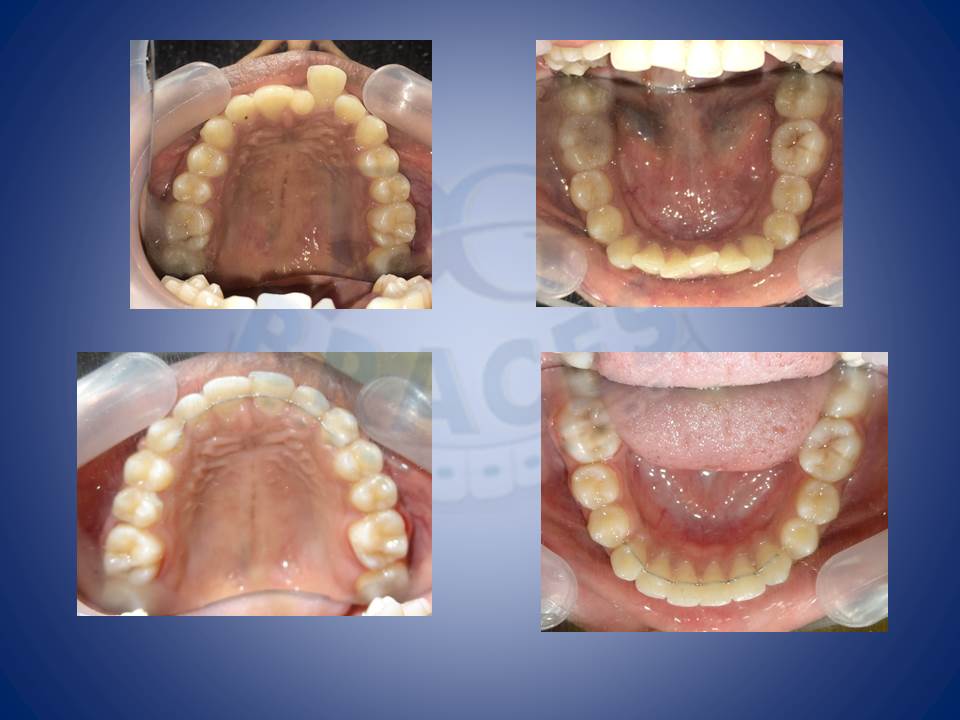

2.Crowding and multiple mutilated teeth are best left treated helping maintainance easy and improving the biting efficiency of patients upto 80%